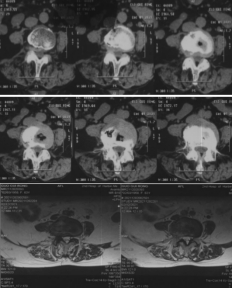

入院后对其进行了详细的检查,发现不仅腰4-5节段有腰椎管狭窄症,还伴有第二腰椎、第五腰椎两处椎体骨折,同时在高血压的基础上又发现了因长期卧床、活动不够而出现的下肢肌间静脉血栓。这些因素导致手术和麻醉风险增加。

腰椎CT、核磁可见腰4-5椎管狭窄